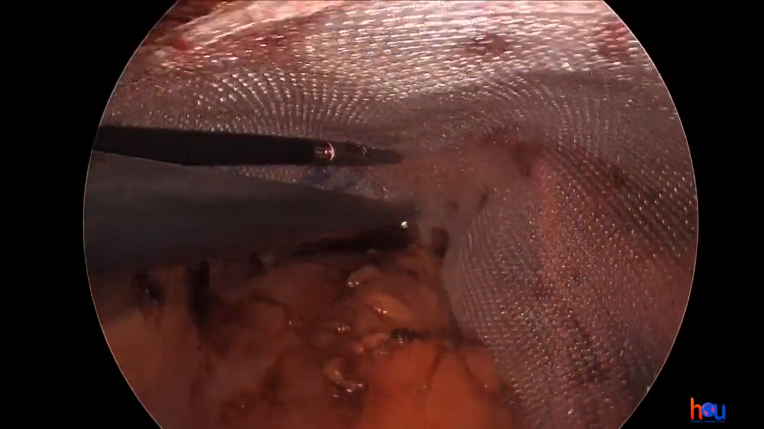

Dr. Malcher | Robotic repair of incarcerated inguinal hernia using CO2 asperation tip

Doctor(s): Dr. Malcher Description of of the case: Robotic repair of incarcerated inguinal hernia using CO2 asperation tip Products Used: Ventralight™ ST Mesh [...]